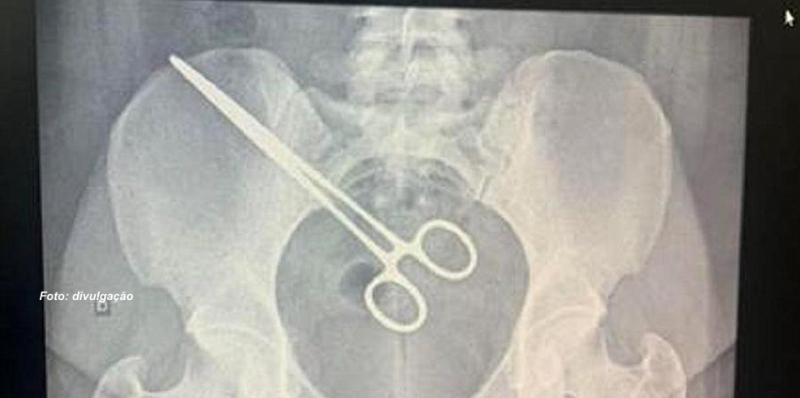

Uma mulher de 27 anos levou um grande susto, no último fim de semana, quando foi visitar o companheiro no Centro de Detenção Provisória de Rio Preto. Ao passar pelo scanner corporal, o aparelho detectou que a visitante tinha uma tesoura no útero.

Ao ser levada para uma sala reservada e lhe apresentarem a radiografia, a mulher relatou que teve uma gravidez ectópica (gerada nas trompas) e sofreu uma forte hemorragia no início de setembro. Foi internada na Santa Casa de Araçatuba, onde passou por cirurgia.

Bastante assustada, ela teve que passar por uma nova cirurgia na Santa Casa de Araçatuba para retirada do objeto. Segundo ela, um pedaço do intestino teve que ser retirado porque foi perfurado pela pinça. Mas, ela já se recupera no quarto.